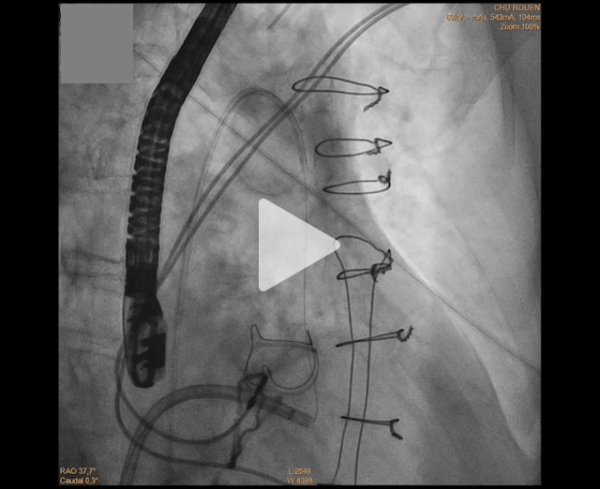

Sous guidage fluoroscopique et échographique transœsophagien, un guide de radiofréquence est introduit par voie rétroaortique pour perforer la base du feuillet antérieur.

Celui-ci est capturé par un guide transeptal, formant une boucle entre les commissures mitrales.

La portion dénudée du guide est ensuite électrifiée, permettant une lacération longitudinale contrôlée du feuillet antérieur le long de sa ligne médiane.

Réalisation du LAMPOON : lacération